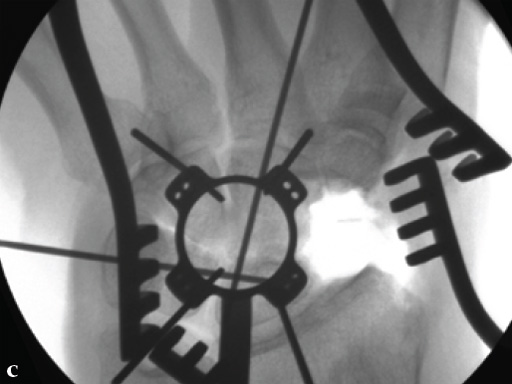

Fig 4c Once the carpal junctions have been putting closer by the new reduction-compression guide, reaming is done.